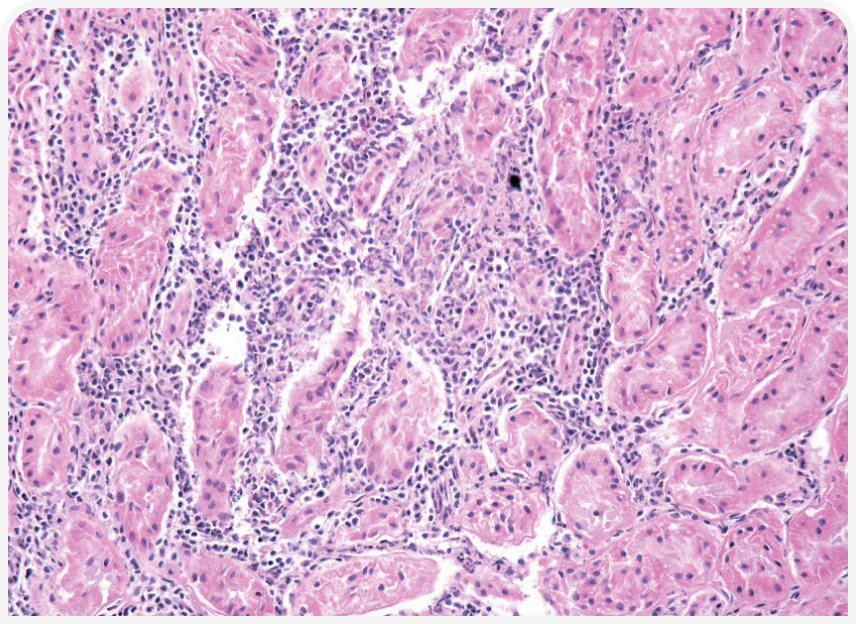

Внутриклеточный рост микроорганизма вызывает прямое цитопатическое действие с воспалением и некрозом клеток хозяина, проявляющееся более специфическими симптомами в зависимости от локализации тахизоитов в организме (Рисунки 4–6); возможны поражение глаз, неврологические симптомы, пневмония, желтуха (4).

Прогноз для кошек с клиническими проявлениями токсоплазмоза зависит от ряда факторов, в том числе от пораженных систем/органов (Рисунки 7 и 8) и времени, прошедшего от момента заражения до начала лечения. Как правило, если в течение 2–3 дней после начала терапии клинические проявления улучшаются, прогноз благоприятный, но прогноз при поражении легких или печени неблагоприятный (4).